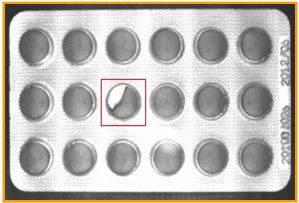

19.药品的缺陷检测

通过机器视觉可以检测药片在包装时可能产生的药片缺损、蚊虫污染、漏装、胶囊漏粉等不良情况进行检测